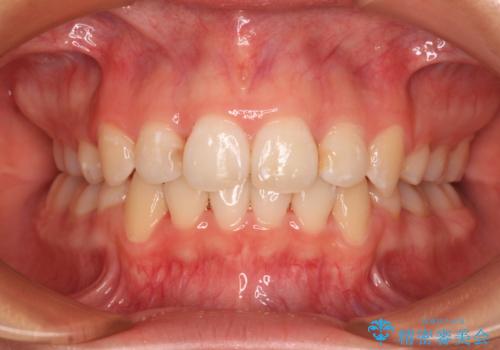

補助装置を併用したおかげでスムーズに奥歯の咬み合わせを改善することができ、我々も予想できないくらい理想的な仕上がりにすることができました。